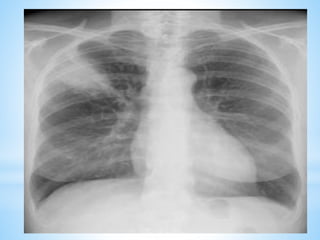

2.1.2. Signes radiologiques

a) Radiographie thorax (face +/- profil)

Doit être réalisée systématiquement

*De profil: topographie exacte de l’opacité

*Nota bene

*peut être normale (les 1ères heures)

*ne peut à elle seule permettre le diagnostic

bactériologique

*au cours de l’évolution, signes radiologiques

sont en retard par rapport à la clinique.